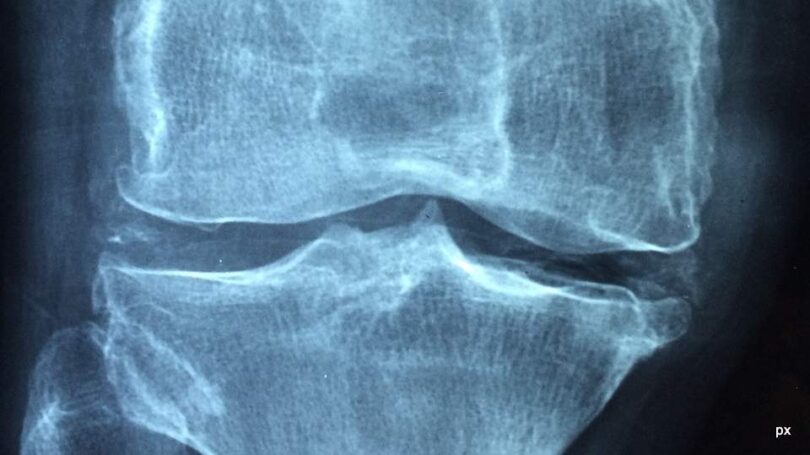

fot. px/zdjęcie poglądowe